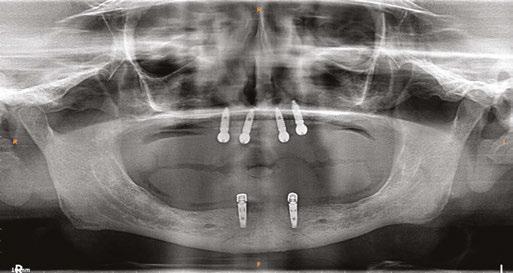

on the crest of the ridge in the region of teeth Nos. 15-25. While creating the incision, bleeding was noticed in the region of tooth No. 15 which intensified during the flap reflection (Figure 2). Bleeding was pulsatile, indicating an arterial bleed. Initially attempts to control bleeding included a pressure pack and ice pack, and the bleeder was isolated and the vessel ligated (Figure 3). The bleeding could be controlled, and the procedure was completed by placing four Bioner implants (Bioner, Spain), size 4/10 mm. Sutures were placed, and patient was kept on basic medication for pain and infection control. Immediately after the surgery, the patient was advised to get a CBCT. As shown in Figure 4, a coronal view and Figure 4B (yellow arrows), the position of the artery can be seen.

In the follow-up sessions, the patient was comfortable, but did complain of mild swelling which subsided within 4-5 days. A post-op CBCT showed excellent recovery, bone width, and proper implant placement (Figure 5).

Figure 2 (left): Alveolar antral artery (AAA). Figure 3 (center): The artery has been ligated with suture. Figures 4A and 4B (right): CBCT post-implant placement and position of the artery coronally (top). 4B. Showing the position of alveolar antral artery (AAA) in relation to implant placement as indicated by the yellow arrows (bottom)

Figure 5: Panoramic radiograph following implant placement